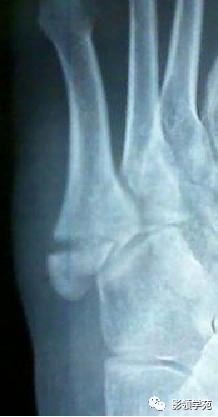

男 26岁 外伤,X线诊断第5跖骨基底部骨折,未排右足骰骨撕脱骨折

三角骨

三角骨是常见的变异,也被误称为距骨副骨。呈三角形, 与距骨后缘相切,三角骨与距骨后突外侧结节腓侧隐窝相对应。

-

三角骨可以成对存在,还可以与外侧结节融合,形成单一的突起,并可与距骨融合或形成关节。

正常变异:距骨三角骨

第五跖骨粗隆

第五跖骨基底部骨折,常为横行骨折,即骨折线垂直于跖骨骨干,它是由于腓侧短肌肌腱应力所引起的撕脱骨折,也称“JONES骨折”。该骨折应与第五跖骨粗隆突起鉴别,尤其是9-15岁的儿童,常常可以出现第五跖骨基底部的骨骺,常表现为纵行透亮线,骨片边缘一般规则光滑,周围软组织无明显肿胀。

第五跖骨粗隆存在独立的骨化中心,并且可有一个或多个骨化中心,常见于10~15岁儿童。一般25岁左右与第五跖骨其余部分融合。

我们所常见的第五跖骨基底部骨折的骨折线一般都是垂直于长轴的,平行于第五跖骨长轴的骨折非常罕见。从外力方向、方式来发现,很难使第五跖骨基底部发生纵形骨折,而该处确实存在骨骺,大量的误诊就是把骨骺当骨折。